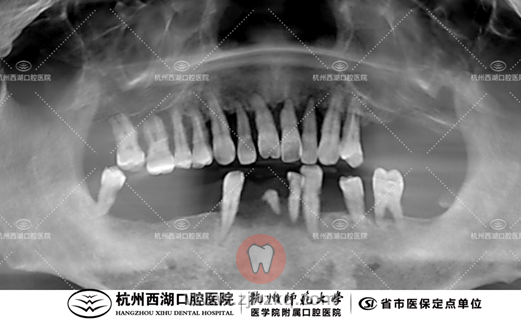

术前CBCT照如下

术后CBCT照如下